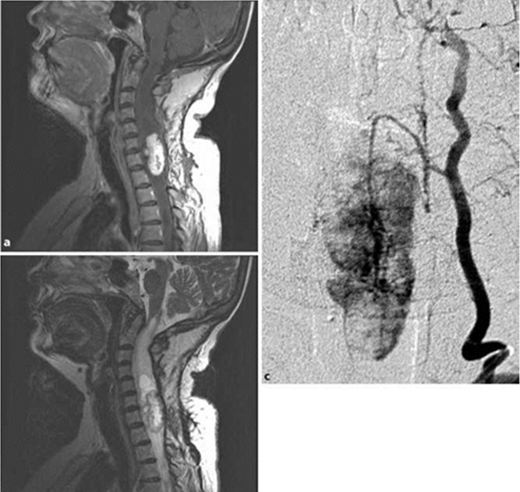

Hình 2: Hình ảnh u nguyên bào mạch máu cột sống.